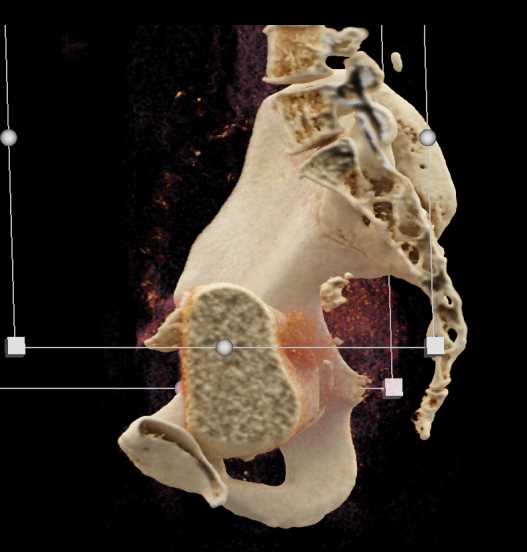

Urachal Carcinoma of the Bladder